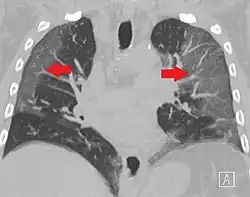

La revista The Lancet publicó el 24 de enero de 2020 un estudio de los primeros 41 casos de pacientes ingresados (en hospital de Wuhan) con el diagnóstico confirmado, desde el 16 de diciembre de 2019 al 2 de enero de 2020.[107] De ellos, menos de la mitad tenían enfermedades subyacentes, entre ellas diabetes, hipertensión y enfermedad cardiovascular. Los síntomas comunes al inicio de la enfermedad fueron fiebre, tos seca y mialgias o fatiga; los síntomas menos comunes fueron la producción de esputo, cefalea, hemoptisis y diarrea. La disnea se desarrolló en 22 de 40 pacientes (55 %), con una mediana del tiempo desde el inicio de la enfermedad hasta la disnea de ocho días. Presentaron linfopenia 26 de 41 pacientes (63 %). Todos los pacientes tuvieron neumonía con hallazgos anormales en la TC de tórax.[117]

La radiología torácica (bien por radiografía, tomografía computerizada o ecografía) puede ayudar al diagnóstico de COVID-19 e identificar o descartar complicaciones pulmonares.[172]